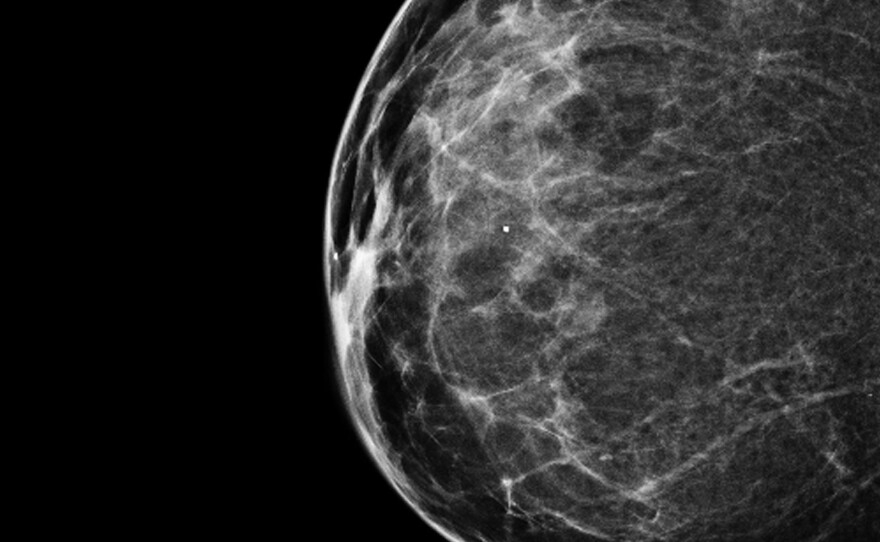

A 3-D mammogram reveals a normal breast.

Both types of tests use X-ray technology to create images of the breast. The 2-D digital mammograms that most women receive typically provide front and side images. For the 3-D test, the X-ray arcs across the breast, creating multiple images of breast tissue. The experience is the same for women, though, because both scans involve compressing the breast between two plates extending from the machine.